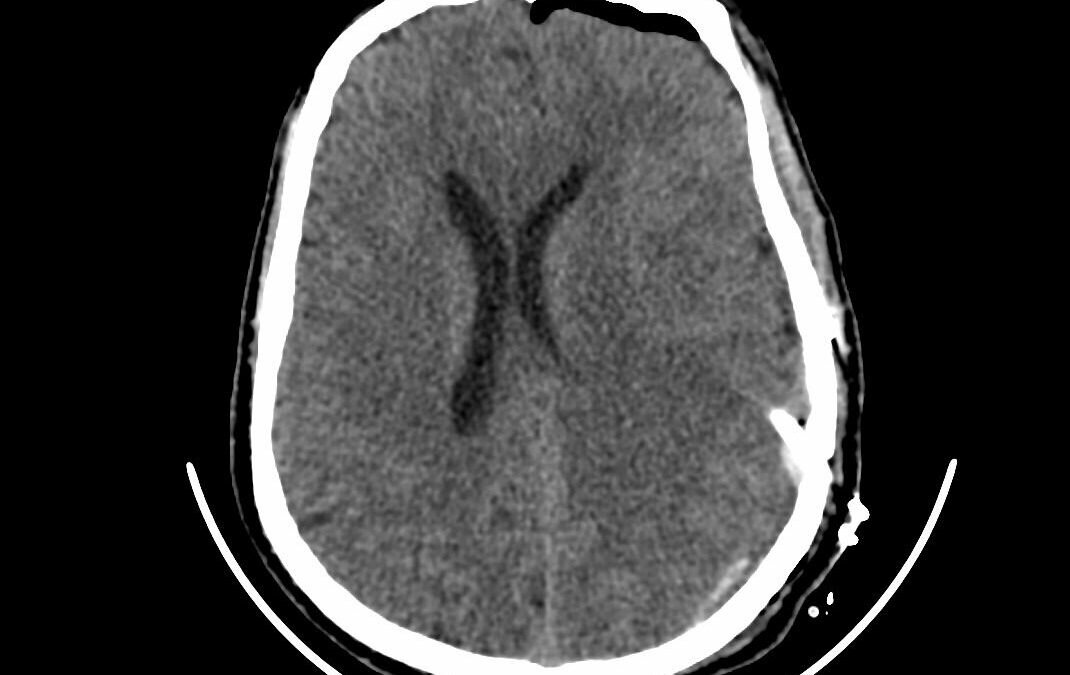

وأوضح رئيس القسم الدكتور زهير هوساوي الذي أجري العملية أن المريض قد قدم لقسم الطوارى وهو يعاني من صداع شديد وفقدان النطق وضعف الحركة بالجانب الايمن من عدة شهور وبعد الفحص السريري والأشعة اتضح وجود اكياس نزفيه بجانب منطقة الحركة والكلام في الدماغ مما استلزم إجراء العملية باستخدام المايكروسكوب والمنظار التي تُعد من أحدث التقنيات العلاجية في هذا المجال وتم ازالة التكيسات في المناطق الدماغية كاملة مع المحافظه على منطقة الحركة والكلام بفضل الله ثم التطور الهائل في مجال الخدمات الطبية والعلاجية الذي تواكبه قطاعاتنا الصحية بدعم واهتمام كبير من القيادة الرشيدة -رعاها الله – وحرصها على توفير أفضل و أحدث الإمكانيات المتطورة تم اجراء العملية بنجاح تام وعودة النطق والحركة لطبيعته السابقة لدى المريض .